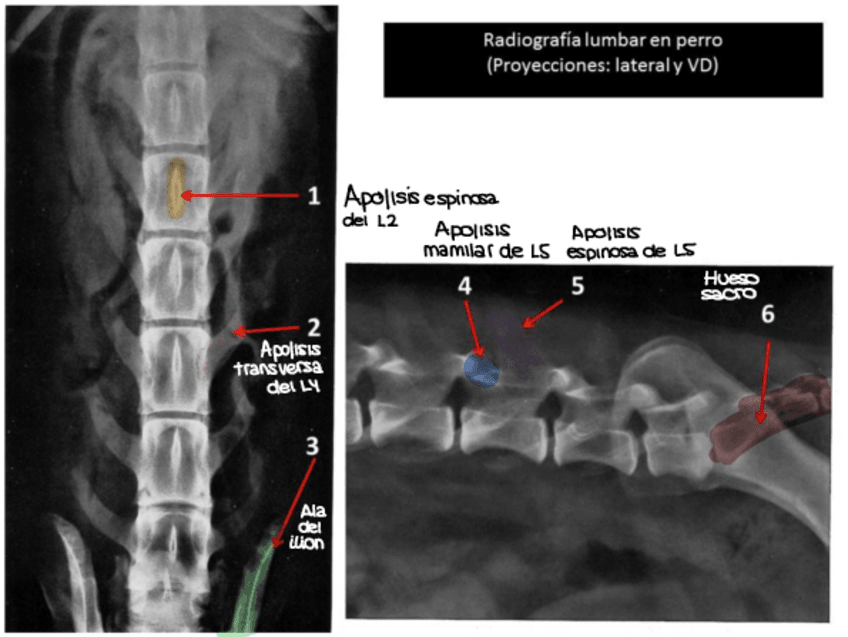

He publicado nuevos apuntes de 1º EMBRIOLOGÍA Y ANATOMÍA I: Radiografías práctica 6.pdf

8 páginas

He publicado nuevos apuntes de 1º EMBRIOLOGÍA Y ANATOMÍA I: SOLUCION-RADIOGRAFIAS-COMPLETAS.pdf

61 páginas

He publicado nuevos apuntes de 1º EMBRIOLOGÍA Y ANATOMÍA I: Todas-las-radiografias-de-anatomia-para-estudiar.pdf

129 páginas

He publicado nuevos apuntes de 1º EMBRIOLOGÍA Y ANATOMÍA I: TEST-3-radiografias-corregido.pdf

5 páginas